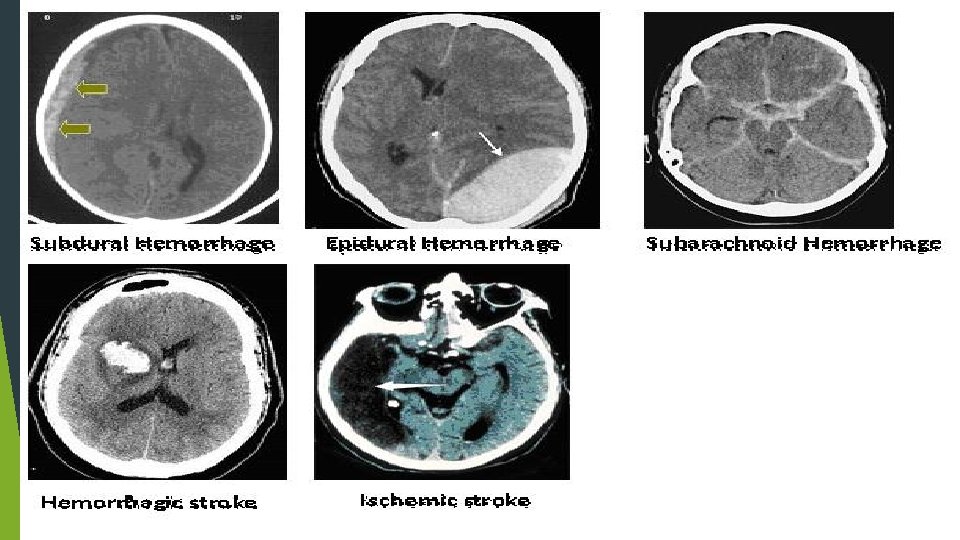

CLASSIFICATION Ischemic Stroke 87% 80% thrombotic 20% embolic Hemorrhagic Stroke 13% 97% intracerebral 3% subdural

IMAGING CT…reliable for intracranial hemorrhage close to 100% sensitive not sensitive for ischemic CVA…especially early MRI…diffusion weighted hyperdense regions of ischemia can detect ischemia after 5 -10 minutes time consuming…. cooperation issues ECHO…echocardiography can identify source of cerebral emboli identify patent foramen ovale